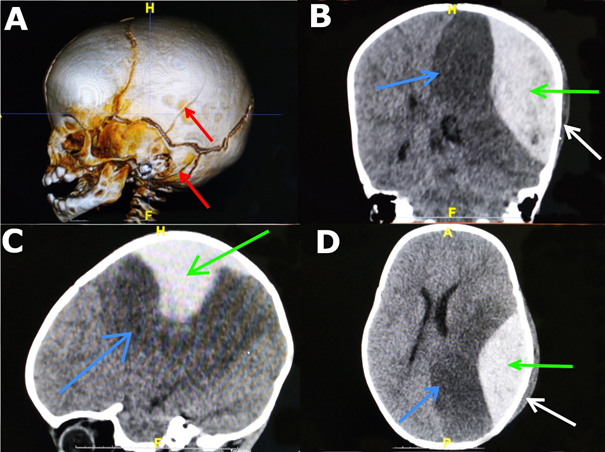

At the hospital, the patient obnubilated with pediatric Glasgow Coma Scale (GCS) score of 12/15 (E3V4M5) and psychomotor agitation. His spontaneous movements were asymmetric, and his pupils were unequal in size and rapidly reactive to light. He had hemodynamic instability and pallor. Uninjected CT images (Figure 1) revealed a left parietal fracture, a subgaleal hematoma, a large left occipoparietal epidural hematoma with an infarct in the territory of the left posterior cerebral artery and midline deviation. Biological tests revealed anemia, with haematocrit decreasing to 5.12 g/dl. We diagnosed a hemispheric infarction in the territory of the posterior cerebral artery following a subacute epidural hematoma complicated by hemodynamic shock.

Figure 1 CT images of the patient showing: (A) 3D reconstruction of the temporoparietal fractures (red arrows); (B,C,D) parenchymal windows, the epidural hematoma (green arrow), the infarct in the territory of the left posterior cerebral artery (blue arrow) and the subgaleal hematoma (white arrow).